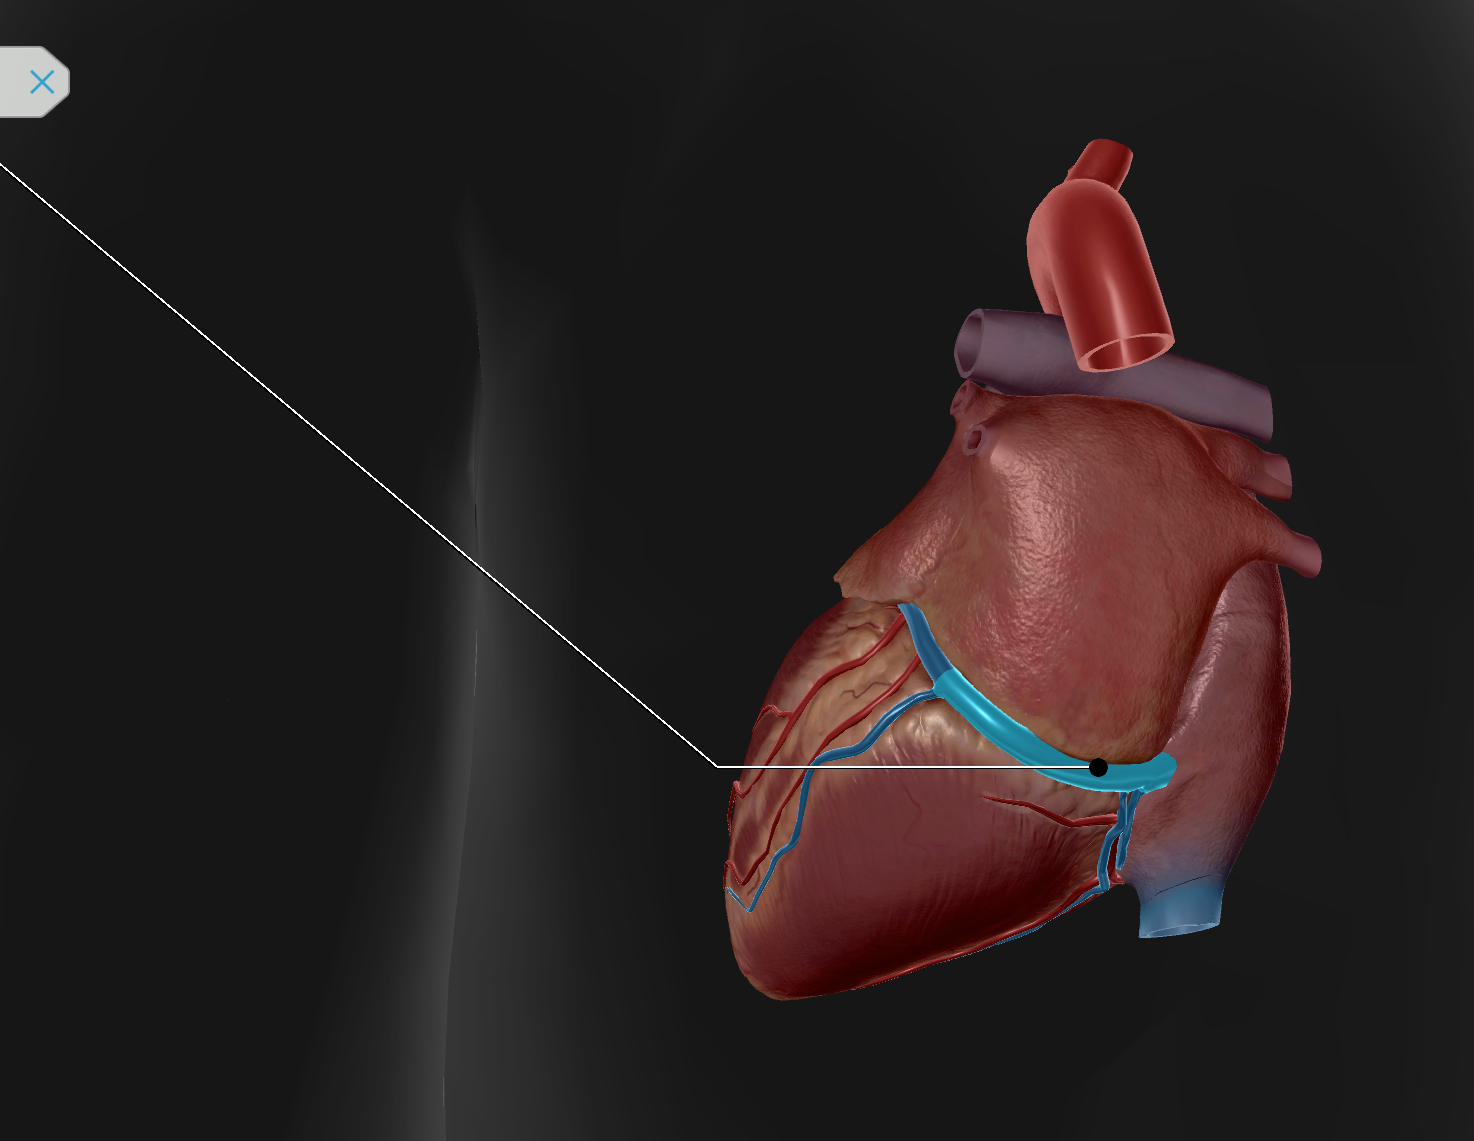

Anterior Interventricular Artery

Circumflex Branch

Coronary Artery

Middle Cardiac Vein

Coronary Sinus

Coronary Sulcus

Small Cardiac Vein

Anterior Cardiac Vein

Coronary Veins

Marginal Branch

Circumflex Artery

Great Cardiac Vein